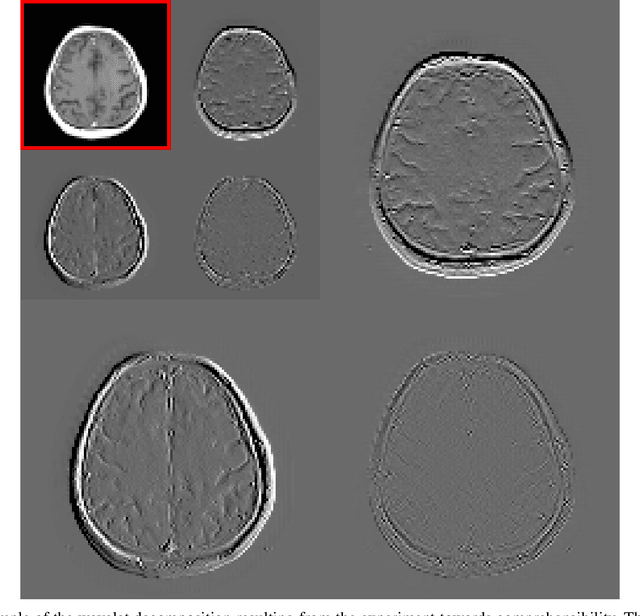

Abstract:Deep learning-based image processing is capable of creating highly appealing results. However, it is still widely considered as a "blackbox" transformation. In medical imaging, this lack of comprehensibility of the results is a sensitive issue. The integration of known operators into the deep learning environment has proven to be advantageous for the comprehensibility and reliability of the computations. Consequently, we propose the use of the locally linear guided filter in combination with a learned guidance map for general purpose medical image processing. The output images are only processed by the guided filter while the guidance map can be trained to be task-optimal in an end-to-end fashion. We investigate the performance based on two popular tasks: image super resolution and denoising. The evaluation is conducted based on pairs of multi-modal magnetic resonance imaging and cross-modal computed tomography and magnetic resonance imaging datasets. For both tasks, the proposed approach is on par with state-of-the-art approaches. Additionally, we can show that the input image's content is almost unchanged after the processing which is not the case for conventional deep learning approaches. On top, the proposed pipeline offers increased robustness against degraded input as well as adversarial attacks.